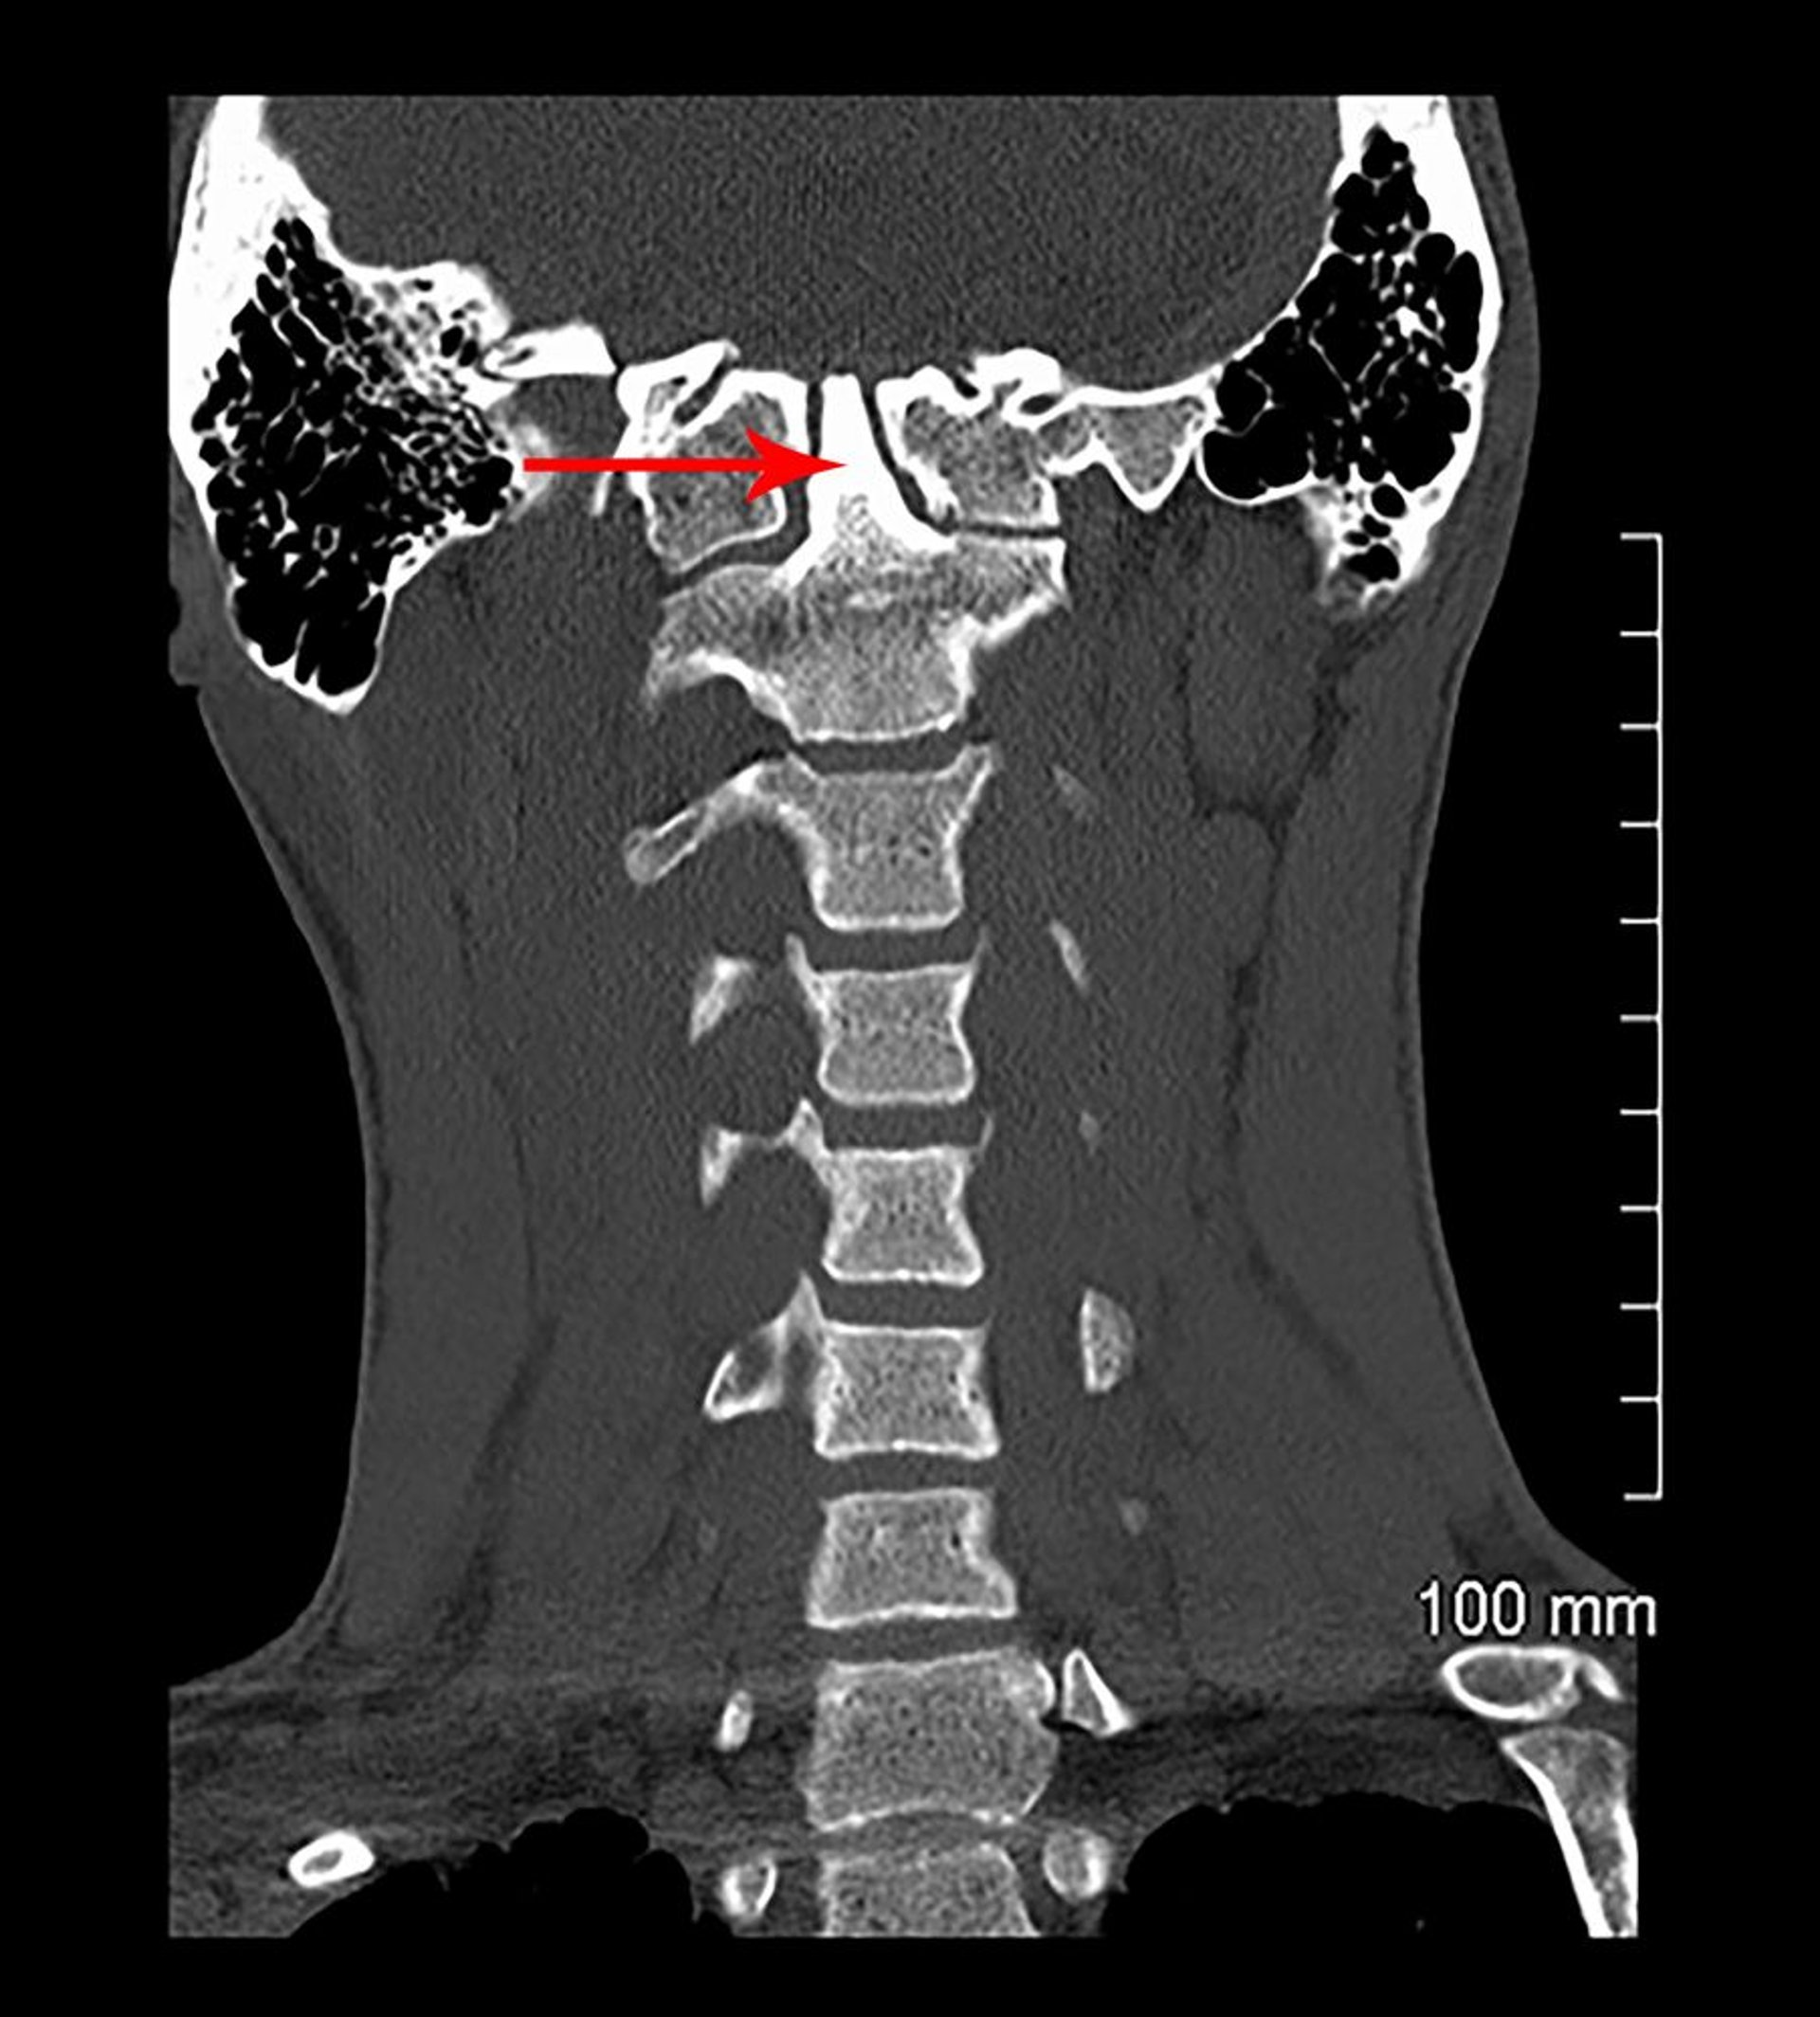

Dans cette vue coronale d'une TDM, C1 est fusionné à la base du crâne (congénitalement). Le processus odontoïde (indiqué par une flèche) s'étend dans la base du crâne (invagination basilaire).